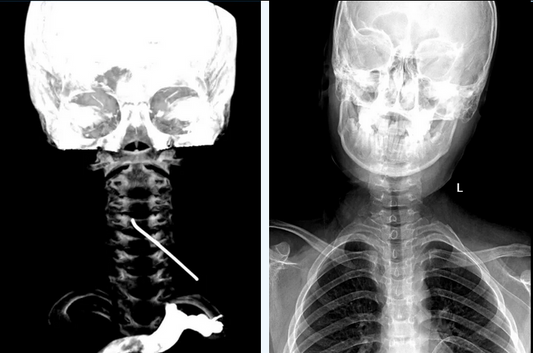

This case highlights a 68-year-old female patient whose neurological status rapidly deteriorated to complete hemiplegia despite medical therapy. The Expert Team at Beijing Fuwai Hospital successfully restored TICI Grade 3...